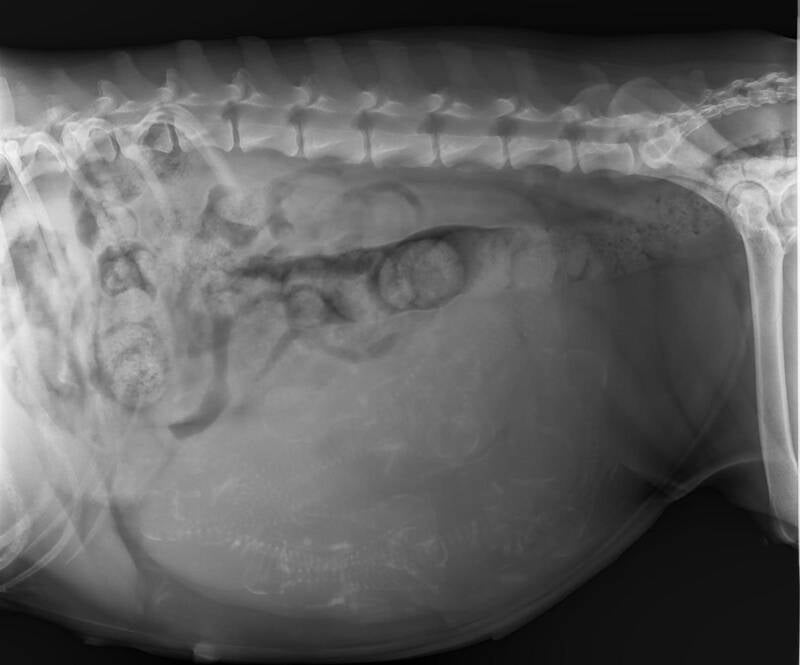

Bezoek aan de dierenarts - juni

Sharlie kreeg vandaag een check-up bij de dierenarts en alles verloopt prima! Ze is in topvorm en stilaan klaar voor haar grote moment. Het aftellen naar de geboorte van haar pups is officieel begonnen!